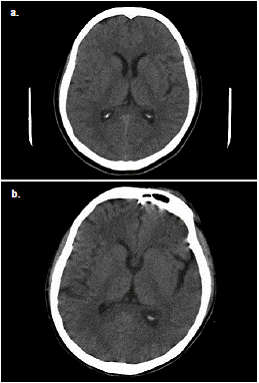

En la valoración psiquiátrica se diagnosticó un episodio psicótico agudo y se inició el tratamiento con lorazepam y risperidona. Los síntomas continuaron con somnolencia, disartria y taquicardia. Se practicaron una tomografía axial (TC) cerebral simple (figura 1) y una resonancia magnética (RM) cerebral simple, cuyas imágenes no mostraron lesiones agudas.